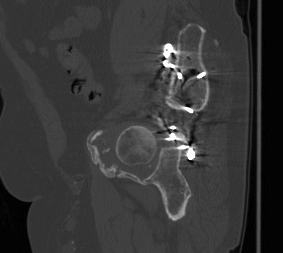

ORIF

Aim

1. Anatomic reduction

2. Provisional fixation with lag screws

3. Buttressing with curved reconstruction plates

Techniques

Posterior Column & Wall Fracture

Reduction

- often indirect

- buttress plate from Ischial Tuberosity to Ilium

- contour or use pre-contoured

- screws at plate extremities

- often 2 parallel plates if wall and column fracture

II to ensure screws not in acetabulum